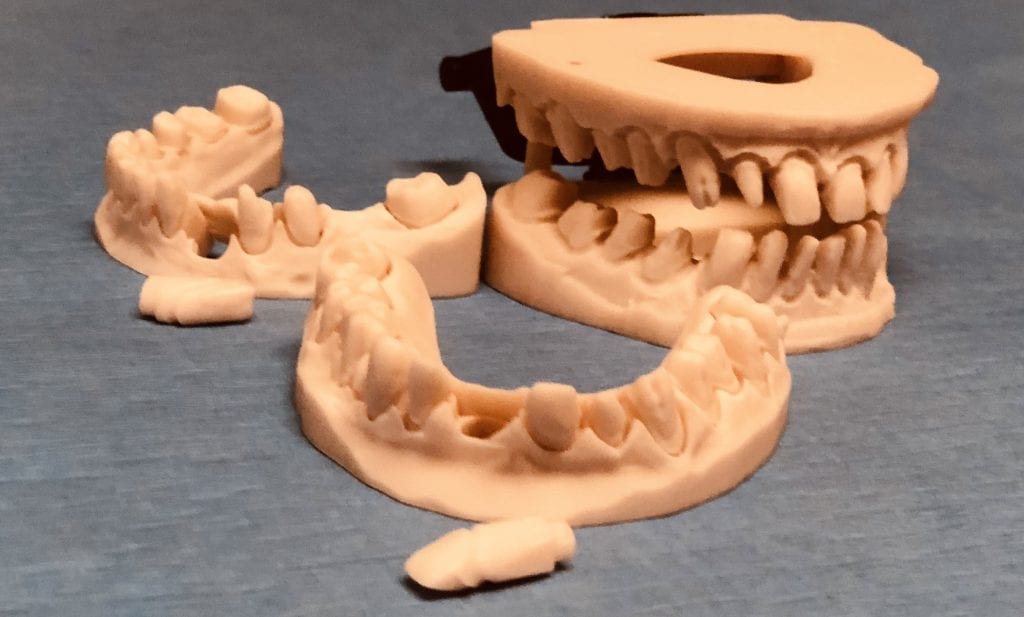

The case was designed by CADENT BESSA, and the models were printed by Burbank Dental Lab with Carbon Printers. There restorations were milled and cut back and layered by Burbank Dental Lab

IMAGES OF PRINTED MODELS